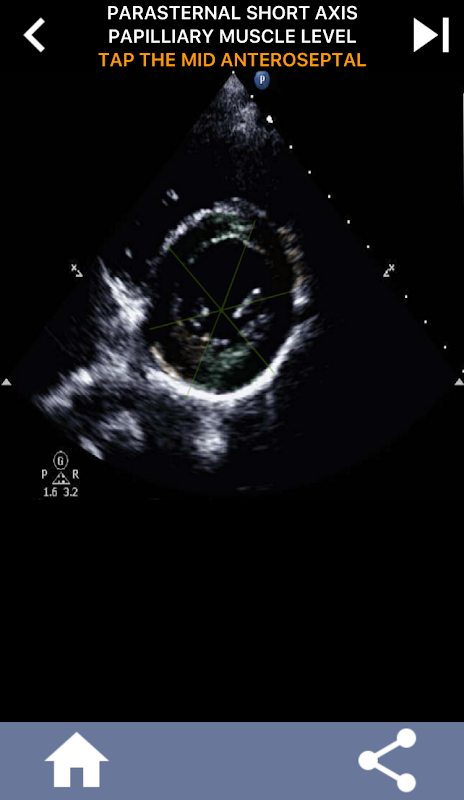

Enfoque visual basado en cuestionarios para aprender los segmentos cardíacos de la AHA: ecocardiografía

Comprender los segmentos cardíacos de la AHA (Asociación Estadounidense del Corazón) es de suma importancia para que un ecografista cardíaco se comunique de manera efectiva con el cardiólogo que escribe el informe. Al conocer las regiones anatómicas específicas y sus segmentos correspondientes, el ecografista puede describir y comunicar con precisión cualquier anomalía o hallazgo, asegurando una comunicación clara y concisa entre ambos profesionales.

Esta comprensión se vuelve particularmente crucial cuando el cardiólogo busca determinar la ubicación precisa de un problema o cuando el médico de guardia identifica un problema dentro de una región específica, lo que hace que el ecografista muestre con precisión el segmento correspondiente, como la pared inferior media. Por lo tanto, poseer una comprensión integral de los segmentos cardíacos de la AHA es un conjunto de habilidades esencial.

Esta aplicación pondrá a prueba su conocimiento utilizando imágenes de eco reales, que a menudo encuentro que es el mejor método de enseñanza.